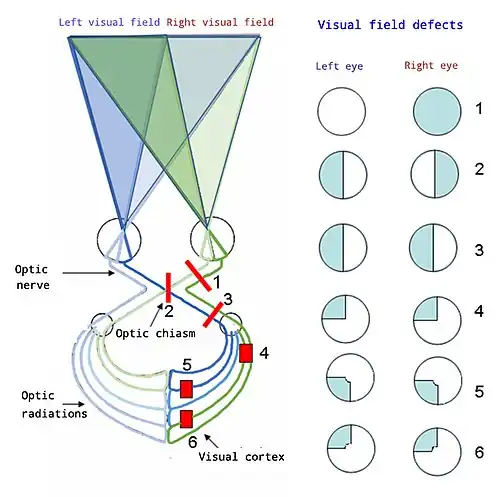

| Visual pathway lesions From top to bottom: 1. Complete loss of vision in the right eye 2. Bitemporal hemianopia 3. Homonymous hemianopia 4. Quadrantanopia 5.& 6. Quadrantanopia with macular sparing | |

The visual pathway consists of structures that carry visual information from the retina to the brain. Lesions in that pathway cause a variety of visual field defects. In the visual system of human eye, the visual information processed by retinal photoreceptor cells travel in the following way:

Retina→Optic nerve→Optic chiasma (here the nasal visual field of both eyes cross over to the opposite side)→Optic tract→Lateral geniculate body→Optic radiation→Primary visual cortex

The type of field defect can help localize where the lesion is located (see picture given in infobox).

- Lesions involving the whole optic nerve cause complete blindness on the affected side, that means damage at the right optic nerve causes complete loss of vision in the right eye.[3]

- A lesion involving complete optic chiasm, which disrupts the axons from the nasal field of both eyes, causes loss of vision of the right half of the right visual field and the left half of the left visual field.[3] This visual field defect is called as bitemporal hemianopia.

Lesions of optic tract

The optic tract is a continuation of the optic nerve that relays information from the optic chiasm to the ipsilateral lateral geniculate nucleus (LGN), pretectal nuclei, and superior colliculus.[14] The optic tract represents the first stage in the visual pathway in which visual information is transferred in a homonymous nature.[15] Main characteristic feature of lesion involving whole optic tract is homonymous hemianopsia. A lesion in the left optic tract will cause right-sided homonymous hemianopsia, while a lesion in the right optic tract will cause left-sided homonymous hemianopsia.

- Lesions of right temporal lobe (meyer's Loop) of the optic radiation on one side produces a loss of the upper, outer quadrant of vision on the contralateral side, known as homonymous superior quadrantanopia or superior quadrantic hemianopia.[25] This is also known as pie in the sky disorder.[3]

- A lesion in the right parietal lobe cause inferior quadrantic hemianopia. It is also known as pie on the floor disorder.[3]

- Occipital cortex lesions tend to cause homonymous hemianopias of variable size, with or without macular involvement.[22]

- Congruous homonymous hemianopia with macular sparing is a feature of occlusion of posterior cerebral artery supplying the anterior part of the visual cortex.[1]